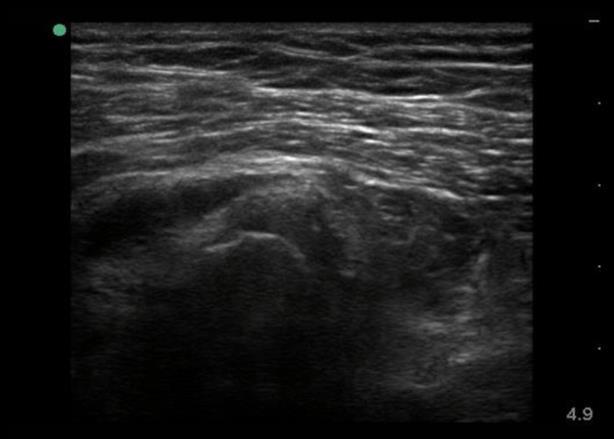

Imagen 1 de la vista axial del lateral de la cadera